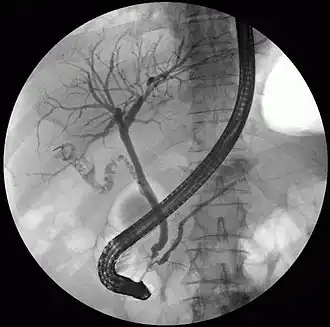

Fluoroscopic image taken during endoscopic retrograde cholangiopancreatography (ERCP). Multiple gallstones are present in the gallbladder and cystic duct. The common bile duct and pancreatic duct appear to be unobstructed.